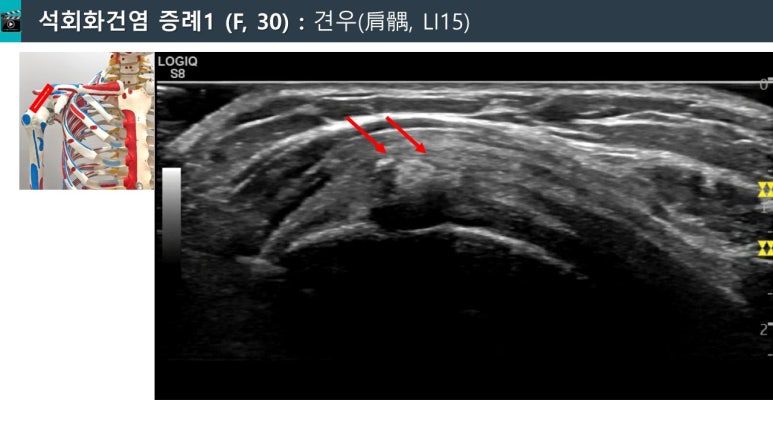

@ 한의영상학회 강연 자료

이 환자분의 을

경혈 초음파로 스캔해보니

표준 경혈 초음파와 달리

힘줄 내부에 하얀 돌이 보입니다.